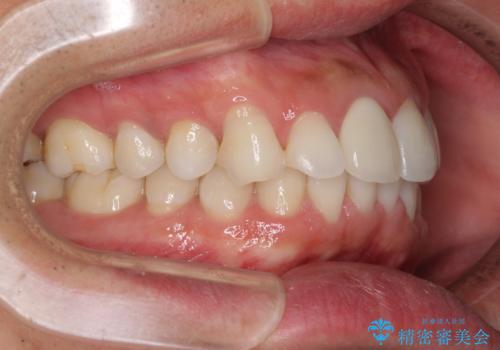

口が閉じにくい インビザラインによる矯正治療

- 口の閉じにくさを気にして来院された患者様です。

患者様と相談の上、横顔の印象から抜歯矯正は必要ないと判断し、IPR(歯と歯の間)並びに歯列全体の後方移動により口元の突出感の改善することとしました。

しっかりと装着時間を守り、ゴムかけも徹底していただいたので、思いの外口元を引っ込めることができました。

これ以上の改善を望まれましたが、非抜歯矯正でこれ以上口元を引っ込めると食いしばりすやすい咬合となるため、この歯列で終了としました。